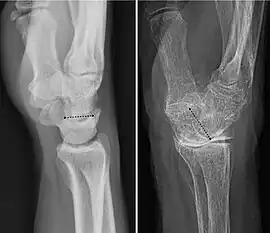

As a consequence of these various definitions, fractures to the carpal bones are referred to as carpal fractures, while fractures such as distal radius fracture are often considered fractures to the wrist.

A wrist fracture usually means a fracture of the distal radius.